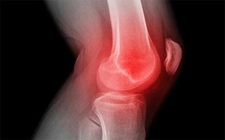

Tanı YöntemleriSağ diz kapağı ağrısının doğru bir şekilde tanımlanması için çeşitli tanı yöntemleri kullanılmaktadır. Bu yöntemler şunlardır: